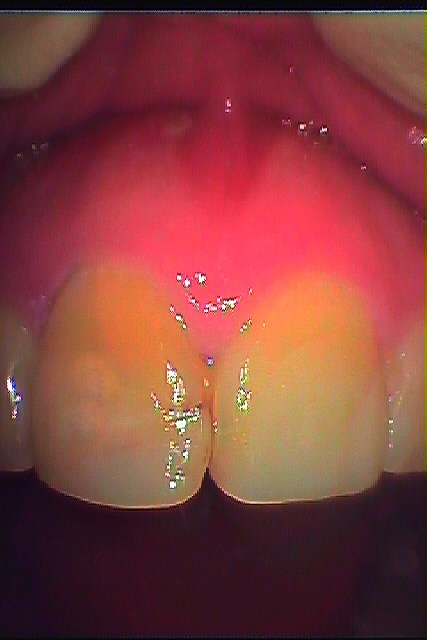

ブログ一覧|広島市安佐南区の歯科医院 ブログ一覧 トップ ブログ一覧 お知らせ スタッフブログ ブログ一覧 お知らせ 2019/04/22 左上3本のソケットリフトテクニックにてのインプラント埋入 上顎洞を挙上して埋入していきます お知らせ 2019/04/22 インプラントの上部構造の破折 最後臼歯のインプラント上部構造 お知らせ 2019/04/20 インプラント埋入より2か月後にいよいよ歯を入れていくようにします お知らせ 2019/04/20 左下奥歯の被せているところが噛むと痛い 歯茎が腫れてきていたい 診てほしい お知らせ 2019/04/19 右上の前歯 神経を取ってあり、色が変わっててセラミックにしてきれいにしたいとのこと 男性の方でした お知らせ 2019/04/19 右下水平埋伏歯の抜歯 動きにくい親知らず お知らせ 2019/04/18 左上最後臼歯のインプラント埋入 上顎洞を持ち上げています お知らせ 2019/04/18 根の治療より3年後、破折歯の抜歯 お仕事の関係で半年後にインプラント埋入 << 1 2 3 4 5 … 415 416 417 418 419 … 870 871 872 873 874 >> Web診療予約 初めての方へ 選ばれ続ける理由 院内設備について 歯が痛いしみる一般歯科 歯がぐらぐらする歯周病 健康な歯を保ちたい予防歯科 子供の虫歯予防をしたい小児歯科 銀歯をセラミックに審美歯科 白い歯を目指しませんか?ホワイトニング 矯正専門医がいるので安心矯正歯科 抜けた歯を補いたいインプラント・入れ歯 医院案内 スタッフ紹介 メリィハウス歯科クリニックオフィシャルホームページ ラベンダー歯科クリニックオフィシャルホームページ お知らせ・ブログ ホーム 診療科目 一般歯科 歯周病治療 予防治療 小児歯科 審美治療 ホワイトニング 矯正歯科 入れ歯・インプラント マウスピース矯正 初めての方へ 院長・スタッフ 設備紹介 医院案内・アクセス メニューを閉じる